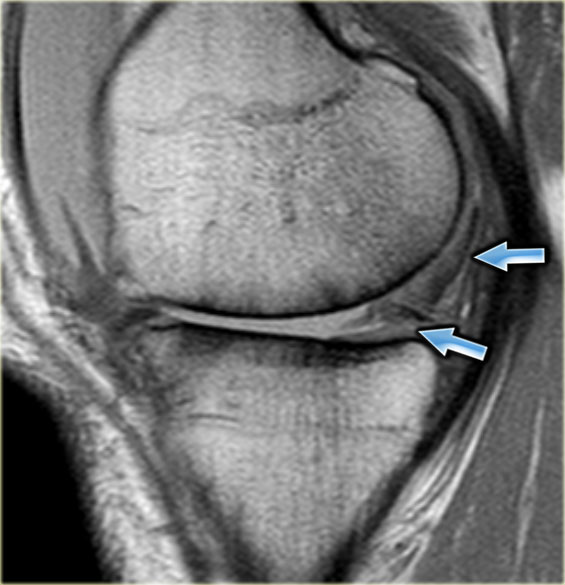

Cùng ca bệnh trên với hình ảnh mặt phẳng sagittal.

Lưu ý phần bị rách của sụn chêm chạy ra phía trước qua hố gian lồi cầu (các mũi tên)

- Thông thường chỉ có hai cấu trúc chạy trong hố gian lồi cầu. Ở đây chúng ta thấy dây chằng chéo sau bình thường.

- Dây chằng chéo trước bình thường.

- Phần bị rách của sừng sau như là ‘cấu trúc thứ ba’

trong hố gian lồi cầu. - Phần bị rách chạy ra phía trước.

- Phần bị rách nhập vào sừng trước và giả tạo hình ảnh rách dọc ở sừng trước.

Lưu ý phần còn lại nhỏ của sừng sau.